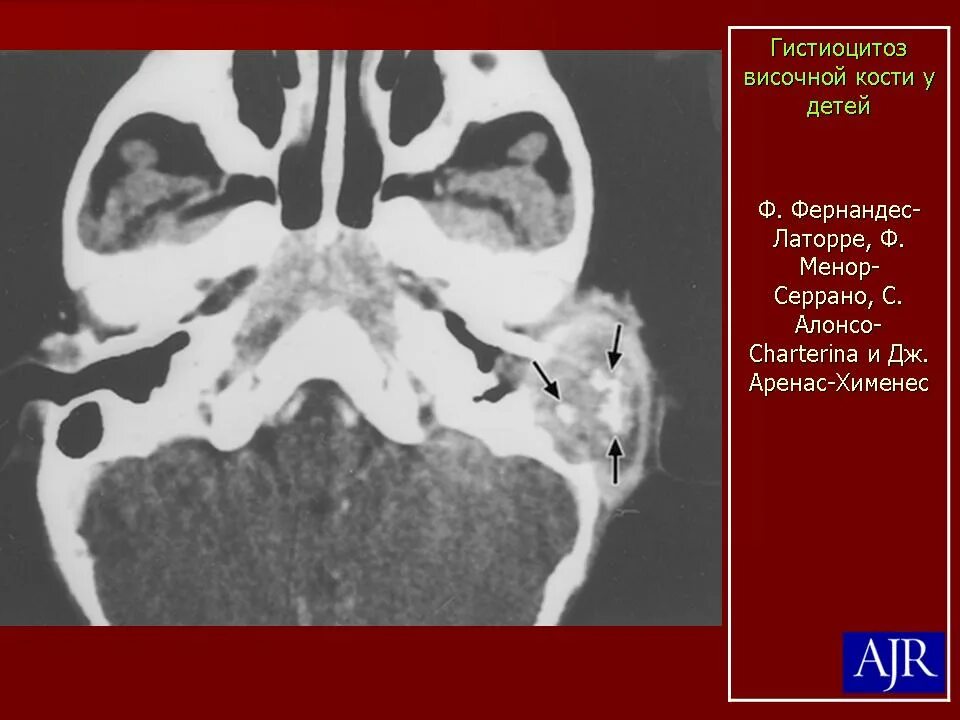

Синусовый гистиоцитоз лимфатического узла